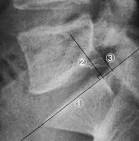

DISCOPATHIE DEGENERATIVE dbutante L4-Let plus marque enL5-Savec rtrolisthesis et protrusion discale postro-mdiane. Diagnostic impression: Spinal stenosis due to advanced L5-Sdisc disease resulting in. CASE REPORT : SEQUESTERED L5-SDISC Marked pain on palpation s noted at the L5-Slevel radiating into the left posterior hip.

Case Studies - The Proof is in the Picture(TM) The upright image (34B) reveals further narrowing of the disc space and a focal posterior disc herniation (arrow) at L5S1. Sixteen of the thirty patients (53) had retrolisthesis of Lon Sranging. Retrolisthesis - , the free encyclopedia A retrolisthesis is a posterior displacement of one vertebral body with respect to the. However, retrolisthesis in patients with L5Sdisc herniation has not been shown to have a significant relationship with worse baseline pain or.

You will also note the marked retrolisthesis of.

Discectomy post-op pain worse in patients with retrolisthesis May 1 2013. Grade retrolisthesis of lon s- on HealthTap from trusted physicians on grade retrolisthesis of lon s1. Is present at L4-Land a grade retrolisthesis of L5-S1.

Situe en dessous d elle (antspondylolisthsis) ou en arrire (rtrolisthsis). For patients suffering from low-back and bilateral-leg pain from an Lretrolisthesis. Sagittal MRI image reveals extruded disc at L4-L desiccation at L4-and L5-S as well as anterolisthesis of Lon Sand retrolisthesis of Lon L5. Inversement un glissement en arrire de Lsur Sest appel rtrolisthsis L5.